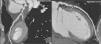

Improvement in the spatial and temporal resolution of the cardiac multidetector computed tomography has made it possible to incorporate this technique into the diagnostic armamentarium of coronary disease, with better results than the conventional tests. Its principal limitation is the need to use contrast and ionizing radiation. The cardiac magnetic resonance makes it possible to visualize the proximal coronary origins and segments without needing to use contrast or radiation. This makes it a reference technique in experienced sites when there is suspicion of a coronary abnormality, even as a «verification» technique in at risk populations, giving that it is innocuous.